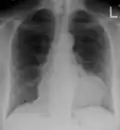

The diagnosis of tamponade can be confirmed with trans-thoracic echocardiography (TTE), which should show a large pericardial effusion and diastolic collapse of the right ventricle and right atrium. Chest X-ray usually shows an enlarged cardiac silhouette ("water bottle" appearance) and clear lungs. Pulmonary congestion is typically not seen because equalization of diastolic pressures constrains the pulmonary capillary wedge pressure to the intra-pericardial pressure (and all other diastolic pressures).